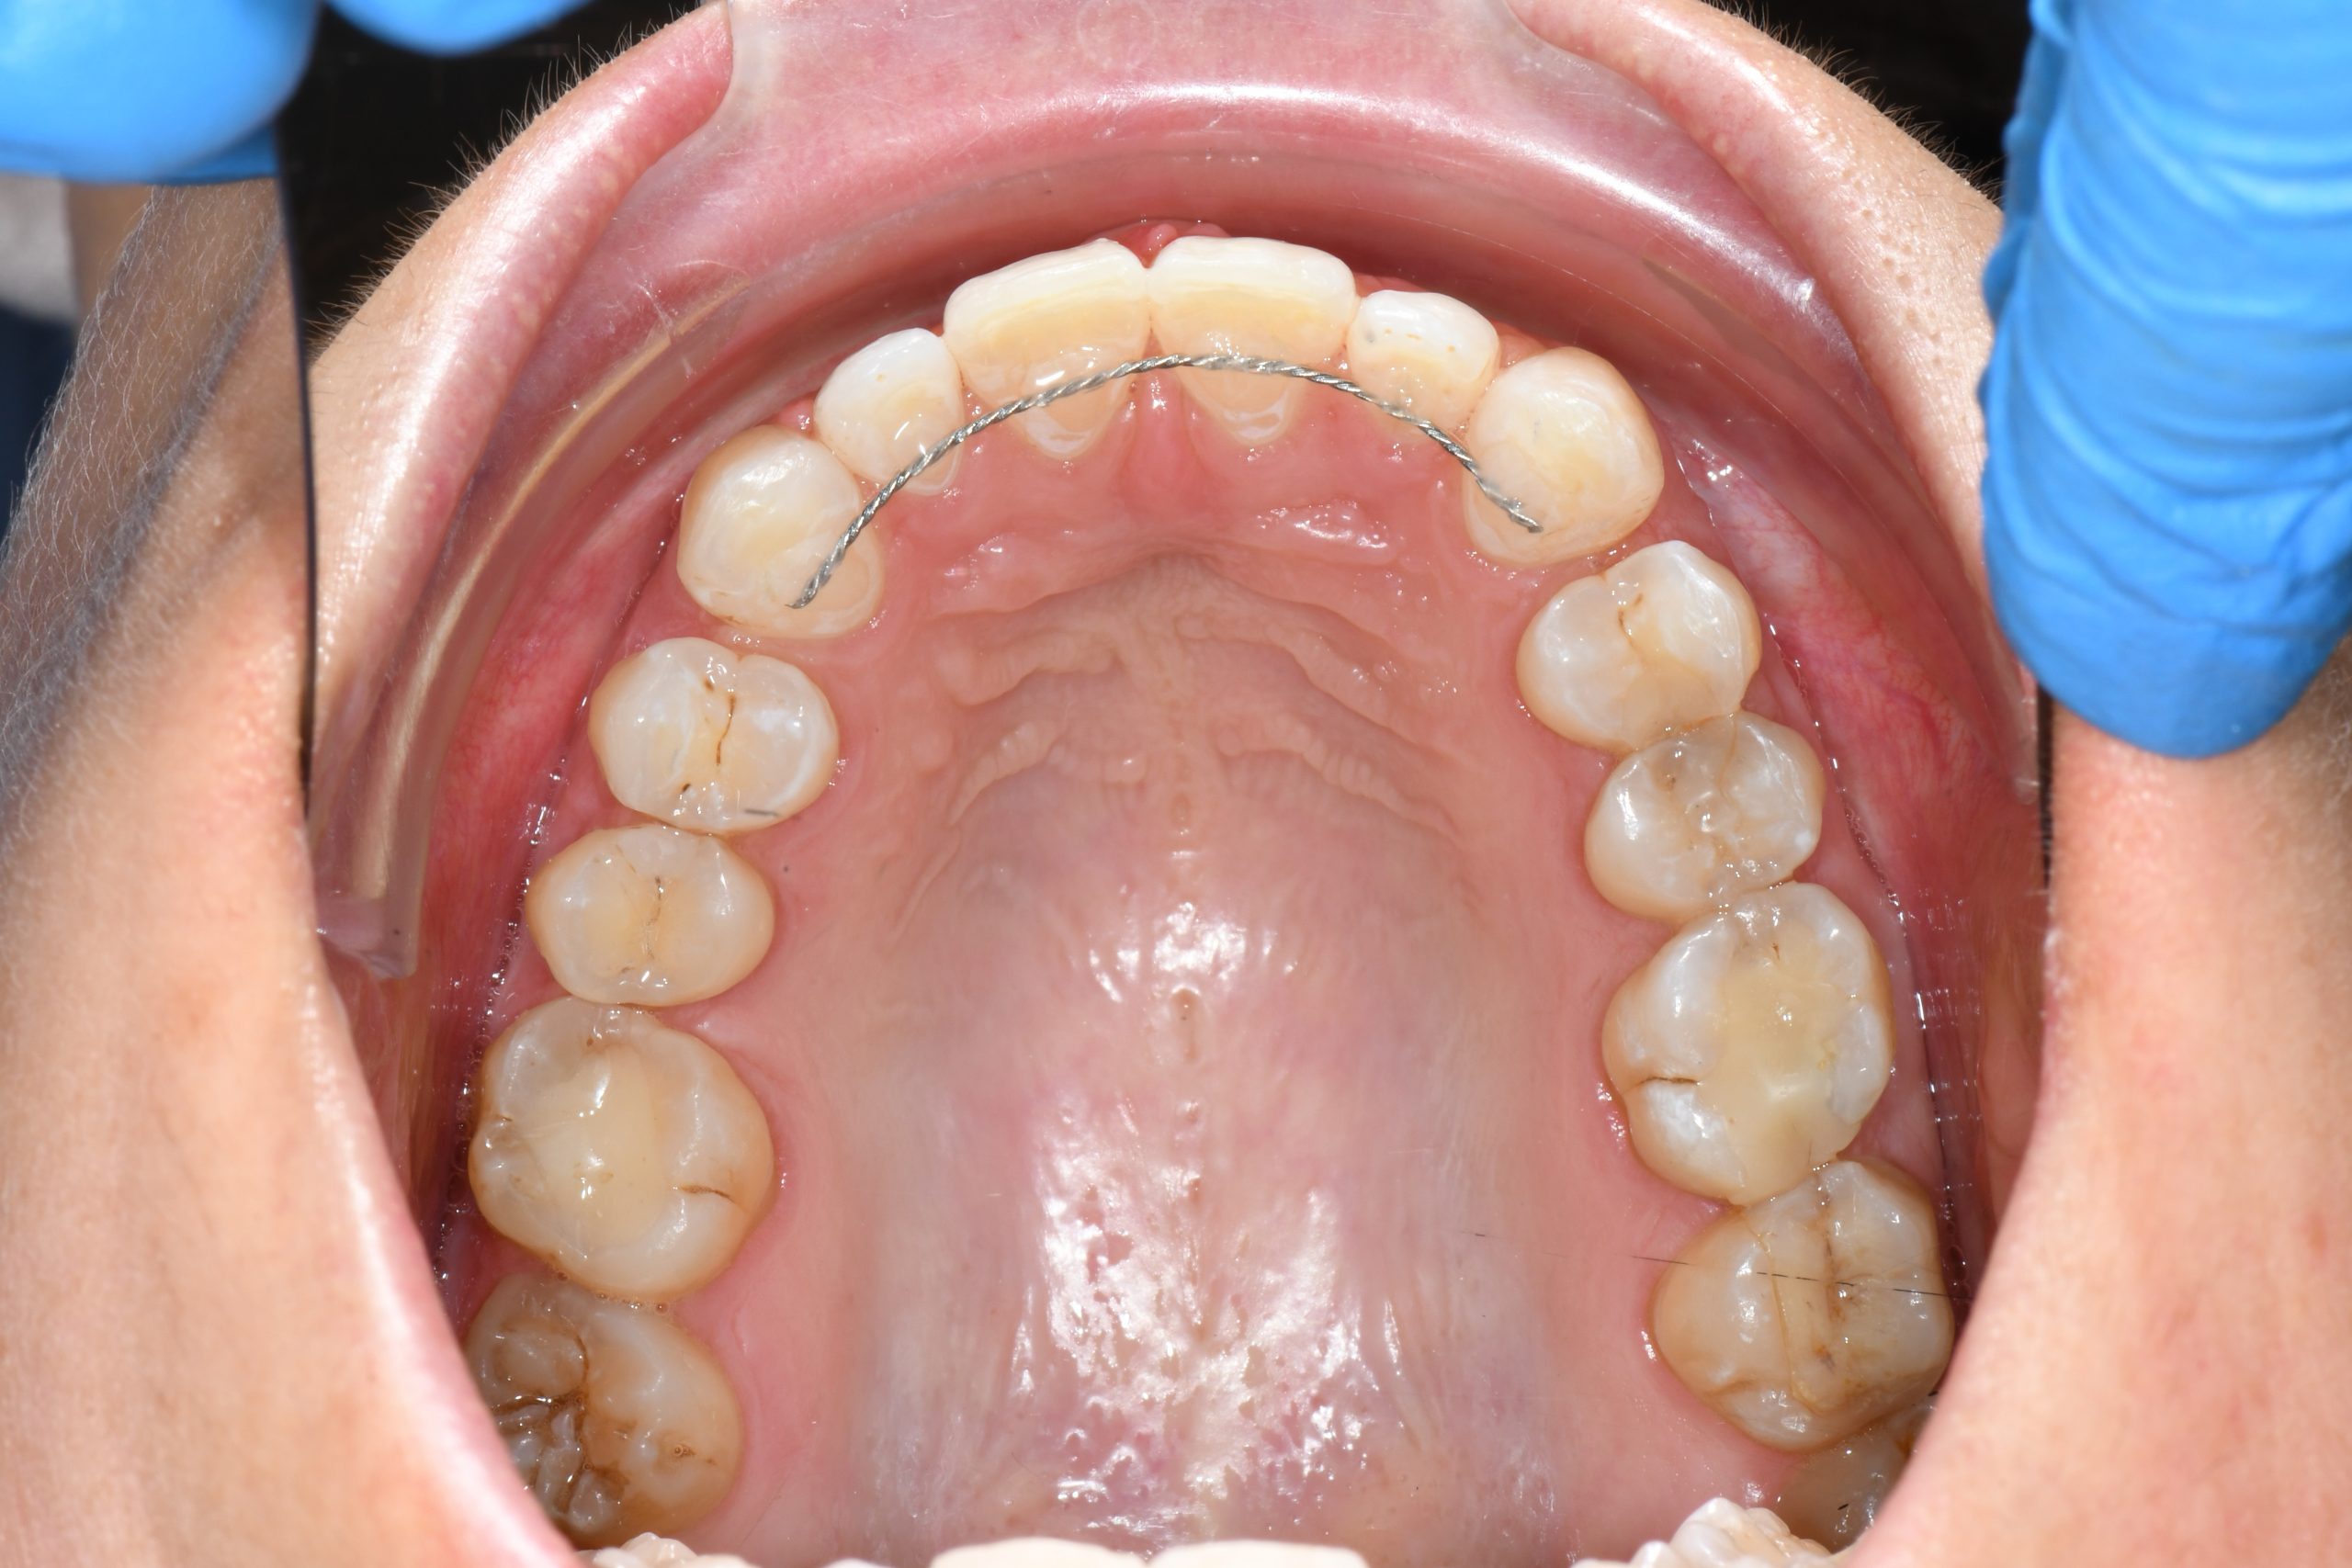

Az elmúlt évekből rengeteg szakmai referenciát tudnánk bemutatni, amelyek különböző fogszabályozási problémákat oldottak meg. Válogatva a több száz esetből, ezen az oldalon olyan képeket, információkat igyekeztünk bemutatni, amelyeknek a segítségével a jövőbeni pácienseinknek azt tudjuk üzenni: A Te fogsorod is lehet gyönyörű!